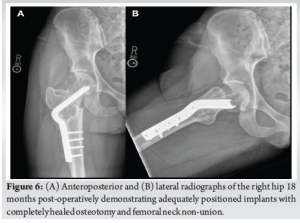

Next, a 20° intertrochanteric valgus closing wedge osteotomy and blade plate insertion was performed. An articulating tensioning device was used to maximize compression at the osteotomy site. Fluoroscopy revealed an acceptable position of all implants (Fig. 5a and b). Post-operatively, she underwent a supervised return-to-activity protocol consisting of partial (50%) weight-bearing with crutches for 8 weeks, following by gradual return to full weight-bearing with physical therapy over 2 weeks thereafter.

She has been followed for 18 months post-operatively. At the most recent follow-up, she has returned to full weight-bearing, along with competitive swimming and daily bicycling without pain. Radiographs demonstrate intact and appropriately positioned implants with completely healed non-union and osteotomy sites (Fig. 6a and b). She has a 2 cm limb length discrepancy, for which she uses a shoe lift.